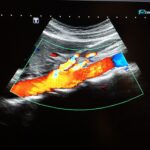

- Doppler de pene